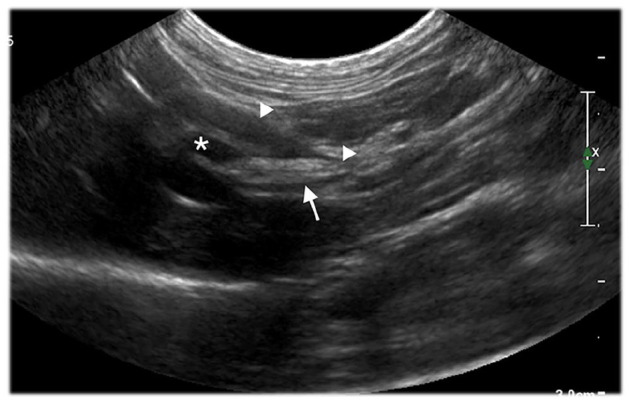

Case summary: A 10-year-old neutered female domestic shorthair cat was presented to our hospital with a 2-day history of anorexia, vomiting and lethargy. The biochemistry panel revealed increased hepatic enzyme activity and serum amyloid A concentration. Haematological values were within reference intervals. An abdominal ultrasound identified a hyperechoic spindle-shaped structure within the common bile duct and a suspected secondary subobstruction, associated with signs of intra- and extrahepatic biliary tract inflammation. During hospitalisation, the cat developed severe and sustained ionised hypercalcaemia. Exploratory surgery was elected as a result of the lack of clinical improvement, despite supportive treatment and suspected retrograde migration of the spindle-shaped structure. Two grass awns were extracted at the junction of an extrahepatic duct and the common bile duct via choledochotomy using intraoperative ultrasound guidance. A stent was then placed in the bile duct to prevent subsequent bile leakage. Histopathology of the liver revealed a moderate neutrophilic and lymphoplasmacytic inflammation with rare bacterial colonies. Escherichia coli was cultured from a bile sample. No specific cause of hypercalcaemia was identified. The cat recovered uneventfully from surgery. Hepatic enzyme activities and hypercalcaemia progressively decreased within a few weeks after surgery and remained within the reference intervals without treatment. Therefore, hypercalcaemia was suspected to be secondary to a foreign body-related granulomatous reaction.

Relevance and novel information: To our knowledge, only one other feline case report of biliary tract obstruction secondary to a biliary foreign body has been described in the literature. This is also the first case reporting the use of intraoperative ultrasound to localise a vegetal foreign body within the biliary tract of a cat. This case is also unique because of the onset of hypercalcaemia suspected to be secondary to a foreign body-related granulomatous reaction.